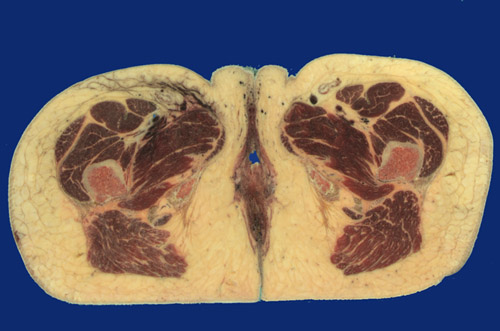

Identify the following regions in the image above: Labia majora - Vestibule - Bulbospongiosus m. - Corpora cavernosa of clitoris - Great saphenous vein - Femoral artery & vein - Adductor longus - Adductor brevis - Adductor magnus - Vastus intermedius - Tensor fasciae latae - Vastus lateralis - Quadratus femoris - Gluteus maximus - Gracilis - Ischium - Femur - Anus - External anal sphincter